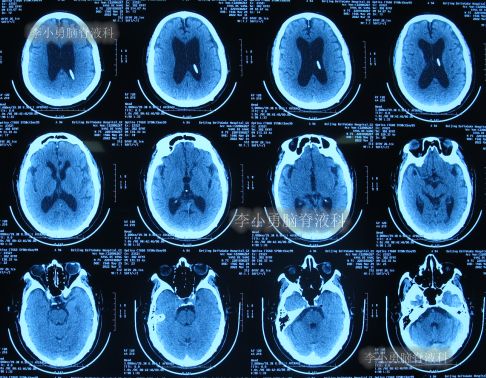

出院后再次转住入当地的第1家医院进行康复治疗,在该院康复治疗半年多的时间,不但没有持续好转,反而再次腰疼,走路不稳,且还出现了尿失禁的持续加重症状;治疗期间曾6次查头部影像(图-13、图-14、图-15、图-16、图-17)均示脑积水不断加重的趋势。

图-13:2021年5月22日头部核磁

图-14:2021年6月2日头部核磁

图-15:2021年7月24日头部核磁

图-16:2021年8月28日头部核磁

图-17:2021年9月28日头部CT